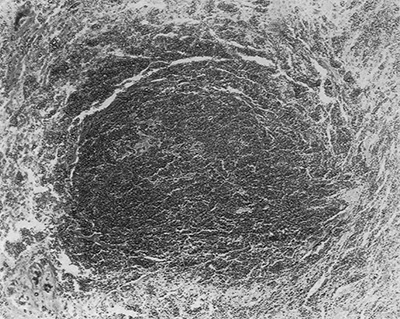

図7. 血液細胞に混じって腫瘍細胞巣が認められる.

図8. 大きなトロトラスト沈着巣

【要旨】70歳⼥性.58歳時に肝の梅毒⾁芽腫(ゴム腫)の診断に際してトロトラストによる動脈造影が⾏なわれた既往があり,その12年後に出⾎性ショックで⼊院,死亡した.

病理所⾒で,肝内転移を伴う出血性の肝腫瘍が認められると同時に,肝内にトロトラスト沈着巣が多発していた(図7,図8).脾,リンパ節,骨髄にもトロトラスト沈着巣が認められた.最終診断は,「多発転移を伴う肝内皮細胞肉腫からの致死的腹腔内出血.肝,脾,リンパ節,骨髄,骨,副腎,腎,血管壁の変性を伴うトロトラスト沈着と放射線障害」 であった.

肝内の最も大きなトロトラスト沈着部位に接して腫瘍が認められた.ホルマリンに12ヵ月水浸した肝ブロック標本をガイガーカウンターで計測すると,トロトラスト沈着部位で最も放射能が強かった.ラジウムによる骨肉腫誘発の臨床例,動物実験例が報告されており,二酸化トリウムによる腹膜肉腫,皮下肉腫の動物実験例もあることから,トロトラストによって肝肉腫が発生したと考えられる.

【解説】トロトラストによる動脈造影の12年後に,肝⾁腫が発生し,その腫瘍内出⾎が原因と考えられた症例報告で,トロトラストと腫瘍の関係については推測の域を出ないが,組織所見および過去の報告を強力な状況証拠として論じ,その因果関係をほぼ断定したという点で画期的な論文である.ただし放射線障害の機序としてはγ線が最も有害であるとしているが,実際にはα線の影響が主である.前掲のBlühbaumの論文でトロトラストが紹介されてから約20年を経ており,これ以前にもトロトラストの腫瘍誘発性については議論されてきたが,潜伏期が長いためにその認識にこれだけの時間がかかり,その間に多くの犠牲者が生まれた.